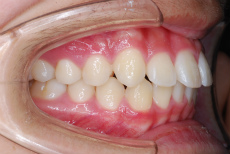

上あご前歯が前方に傾斜しており、しかも相対的に下あごが後退している上顎前突(出っ歯)の状態です。

上下あご共にすべての乳歯が永久歯に交換して数か月後の噛み合わせの状態です。

この時点では上あごの12才臼歯である第二大臼歯がまだ生えていません。つまり、歯並びが整ったこの時点で ”もういいですよ” と治療をとっとと終わらせてしまうのはまだ早い ということです。